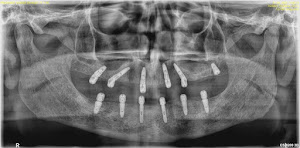

Welcome to our gallery

See how our company transforms ideas into reality. This gallery is a visual testament to our work and achievements.